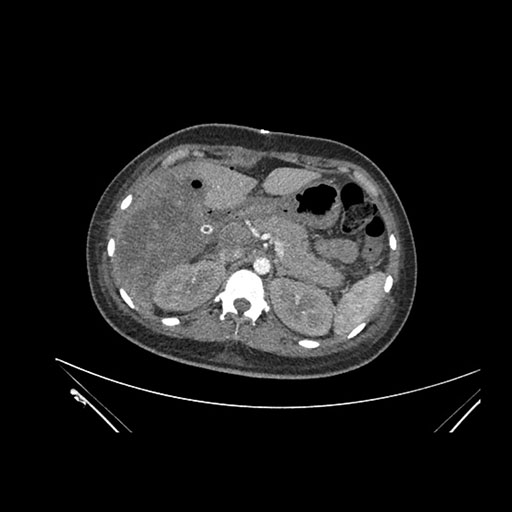

Imaging Analysis

Look through the patient's CT scan to identify any areas of concern for the necessary procedure.

Coronal Arterial

Based on initial findings, which issue(s) would you be most concerned about?